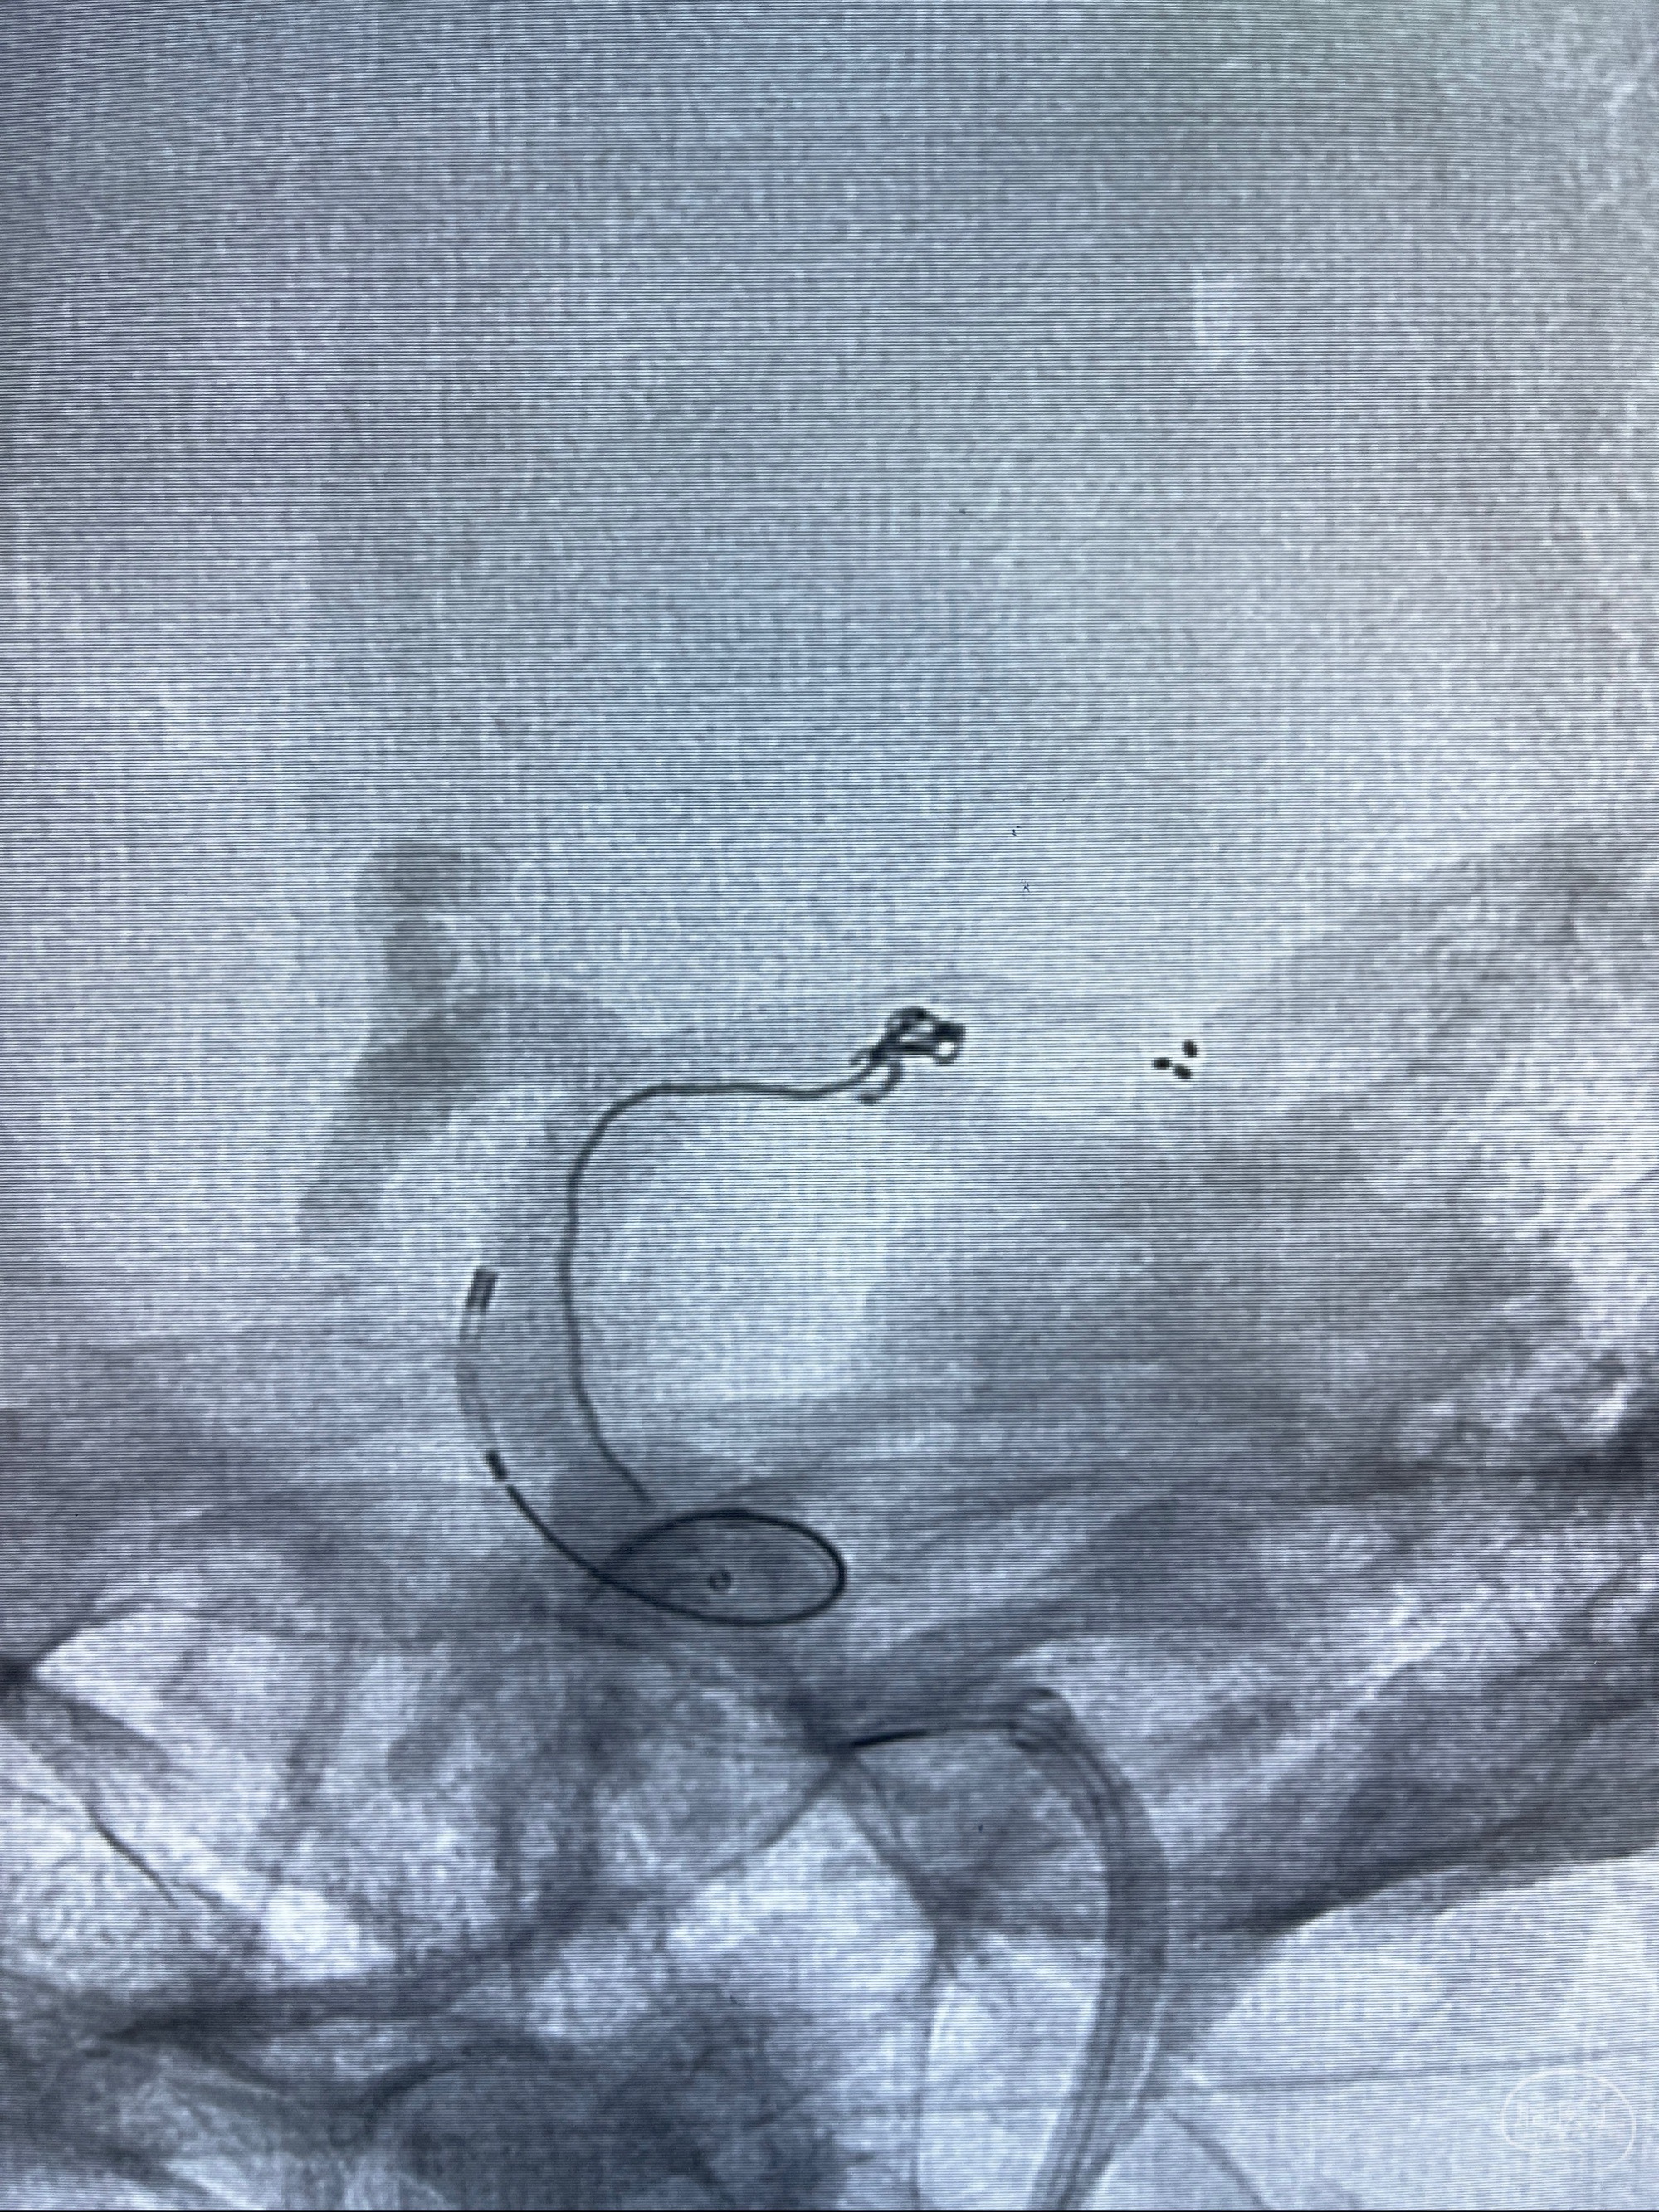

2.外科手术夹闭or介入支架辅助栓塞

麻醉苏醒佳,遵嘱动作